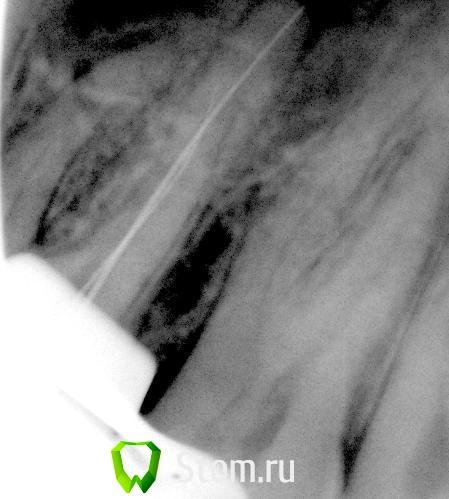

Ferny Опубликовано 30 марта, 2012 Поделиться Опубликовано 30 марта, 2012 помогите пожалуйста, дорогиэ коллеги! зыб 26 периодонтит. раширяла протейперами С1,Сх и потом делала рентген с иголками после показаний апекс локатора. если верит апекс локатору то вот рентген , палатоиналняй за верхущку на 1 мм, а букодисталний канал вобще не доходит до апекса, хотя апекс локатор всё показал . переделала рентген, в палатиналном на 1 мм менще длину поставила а на букодисталном поставила на 2 мм болще. посмотрите...меня интересует букодисталняй...с длиной 19 мм апекс локатор 4тото как то неопределённо показявает то 0,4-0,5...нужно ли в букодисталном идти далще или оставитй так как естй и расщирят его далще? спасибо Ссылка на комментарий